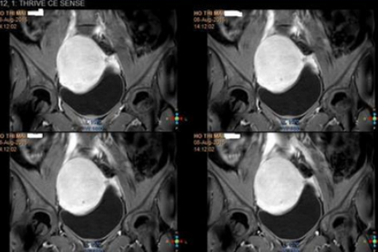

Gần 80% phụ nữ trên 50 tuổi bị u xơ tử cungU xơ tử cung là bệnh thường gặp ở phụ nữ trong độ tuổi sinh sản, đặc biệt là những người ngoài 50 tuổi với gần 80% mắc bệnh. Khoa học chưa xác định được nguyên nhân gây u xơ tử cung nhưng đã có phương pháp điều trị triệt để không cần phẫu thuật.

Từ nỗi lo vô sinh đến niềm vui làm mẹ của bệnh nhân đa u xơ tử cungÔm cậu con trai mới chào đời, chị Trang (30 tuổi) không giấu được niềm hạnh phúc. Ít ai biết rằng, chị từng suy sụp tinh thần khi bị sảy thai ở tuần thứ 20 do mắc đa u xơ tử cung.

Hơn 10 năm bị vô sinh thứ phát vì căn bệnh phổ biến ở phụ nữĐược chẩn đoán mắc đa u xơ tử cung từ hơn 10 năm trước, chị Thanh Lan (43 tuổi) không chỉ phải chịu đựng những triệu chứng khó chịu kéo dài mà còn rơi vào hành trình vô sinh thứ phát đầy trắc trở.